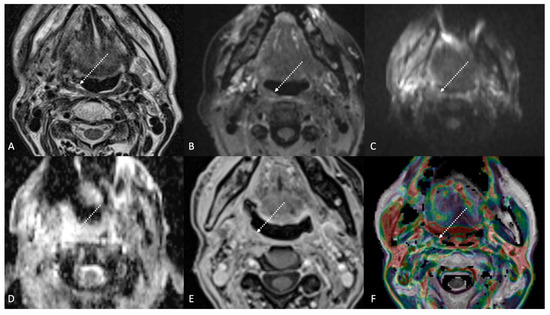

Figure 5.

Post-treatment magnetic resonance imaging (MRI) of a 47-year-old female patient with human-papillomavirus-negative carcinoma of the left palatine tonsil with ipsilateral lymph node metastasis (T4aN1) and buccal space and mandibular invasion, recently treated (4 months before) with chemoradiotherapy (CRT). Early post-treatment MRI showed tumor progression with wide extension to the extrinsic muscles of the contralateral tongue (maximum tumor thickness 45 mm). Post-CRT tumor residual/relapse disease (white striped arrows) showed moderately high (intermediate) T2-weighted signal intensity (A,B), high signal on diffusion-weighted b800 imaging (C), low apparent diffusion coefficient value (0.79 × 10−3 mm2/s, (D), and moderate enhancement after gadolinium contrast injection (E). K(trans) value of the tumor (56.24 × 10−3 min) decreased on dynamic contrast enhancement-perfusion weighted imaging (F), compared to pre-treatment MRI (117.63 × 10−3 min). However, the ratio between K(trans) values of the primitive tumor and residual tissue after CRT, standardized with respect to K(trans) value of the ipsilateral trapezius (K(trans)post/pre/muscle), was 1.14. These findings suggested little or no reduction in tumor neoangiogenesis after CRT.